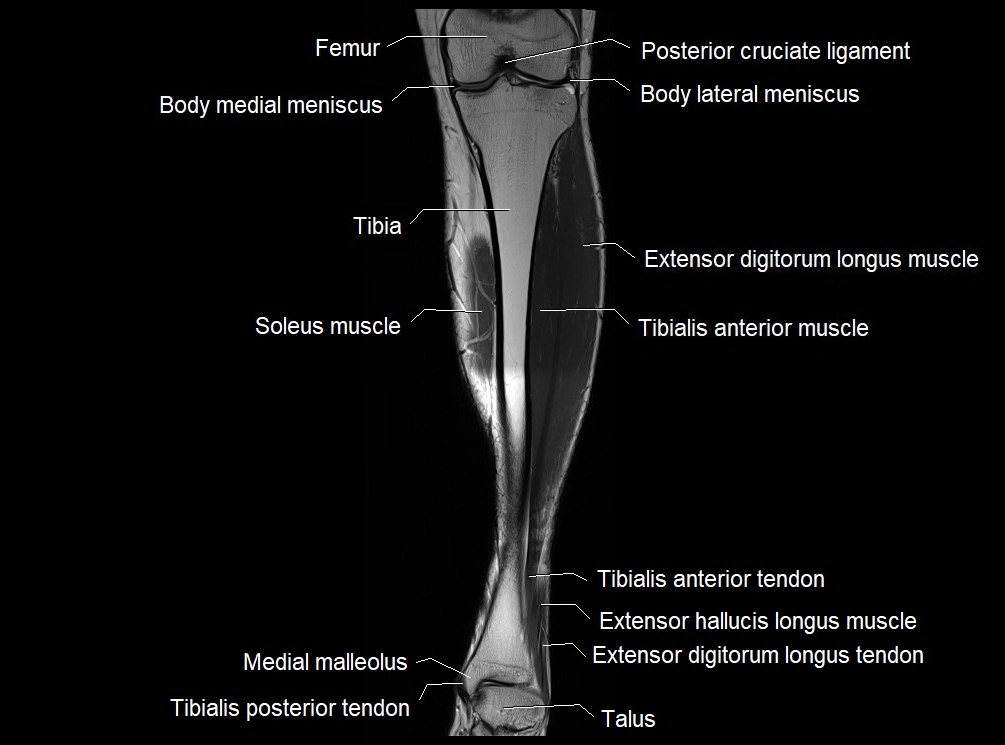

MRI image